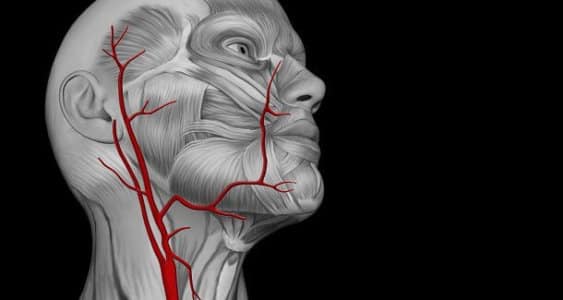

Se per un attimo si immagina un tessuto parodontale infetto, esso appare solcato da piccole ma estese ulcere (da 5 a 20 centimetri quadrati nell’intera bocca) intrecciate fra loro che sono un’importante porta di ingresso nel sangue di batteri parodontopatici. Tra questi, il Porphyromonas gingivalis, servendosi delle propaggini (o fimbrie) di cui sono dotati, si attaccano alle arterie, colpiscono e penetrano sotto lo strato delle cellule endoteliali infettandole.

Le cellule endoteliali colpite, a loro volta, attivano dei composti (catechine) pro-infiammatorie e tutto questo induce alla morte delle cellule endoteliali. Questa fase, denominata “disfunzione endoteliale”, porta ad una perdita di elasticità dei vasi sanguigni.

Associata a questa fase ve ne è una seconda dove i globuli bianchi (leucociti) si differenziano in macrofagi i quali, assorbendo colesterolo, si trasformano in cellule schiumose che si accumulano fino a restringere l’arteria, riducendo ed ostacolando il flusso sanguigno.